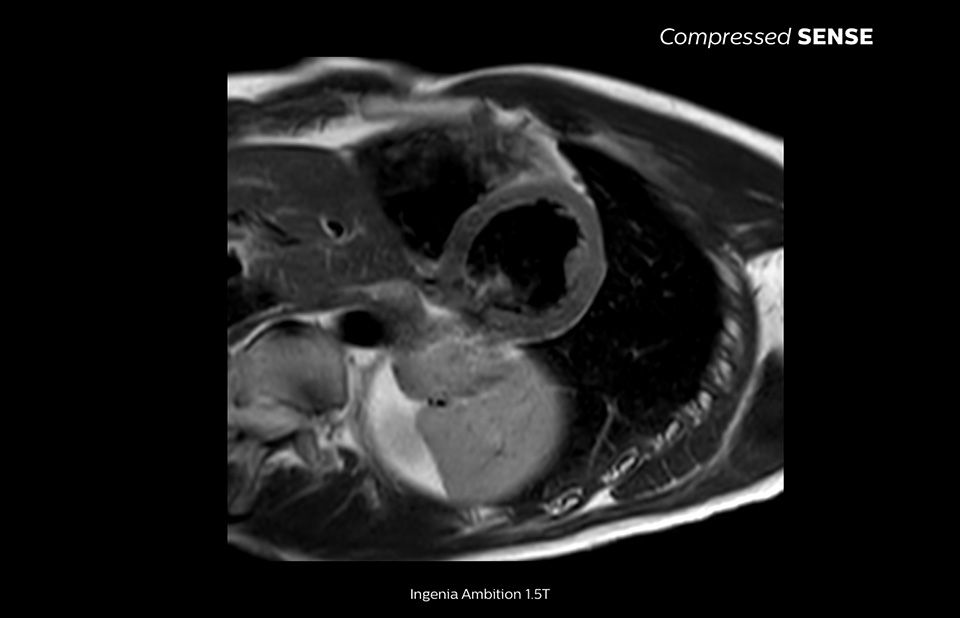

Philips Compressed SENSE verkürzt die Zeit, die ein Patient im MR-Scanner verbringt. Außerdem kann mit Compressed SENSE die Atemanhaltezeit verkürzt werden, was die Patientencompliance bei einem MR-Scan fördert.

4,8 s Atemanhalten

Da kurze Atemanhaltephasen einfacher für unsere Patienten sind, kommt es jetzt fast nicht mehr vor, dass Patienten den Atem nicht lang genug anhalten. In unserer Einrichtung sind bei Kardio-MRTs jetzt weniger Atemanhaltephasen nötig, oder die nötige Dauer der Atemanhaltephasen hat sich verkürzt.“

Eine Atemanhaltephase von 15 bis 16 Sekunden ist für viele Herzpatienten schwierig. Mit Compressed SENSE haben wir jetzt Protokolle, in denen diese Zeit auf unter 10 Sekunden reduziert wurde. Das ist für die Patienten viel einfacher. Die Patienten sind dann mit dem Verfahren auch viel zufriedener.“